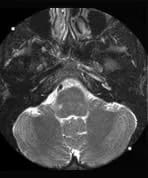

The left internal carotid artery (ICA) is of reduced calibre throughout its extra and intracranial course. In addition there is a marked focal narrowing with a flow gap at its origin. The axial fat saturated images through the petrous portion of the left ICA reveals high signal material surrounding the narrowed lumen. The appearances are suggestive of a partially recanalised dissection of the left ICA.